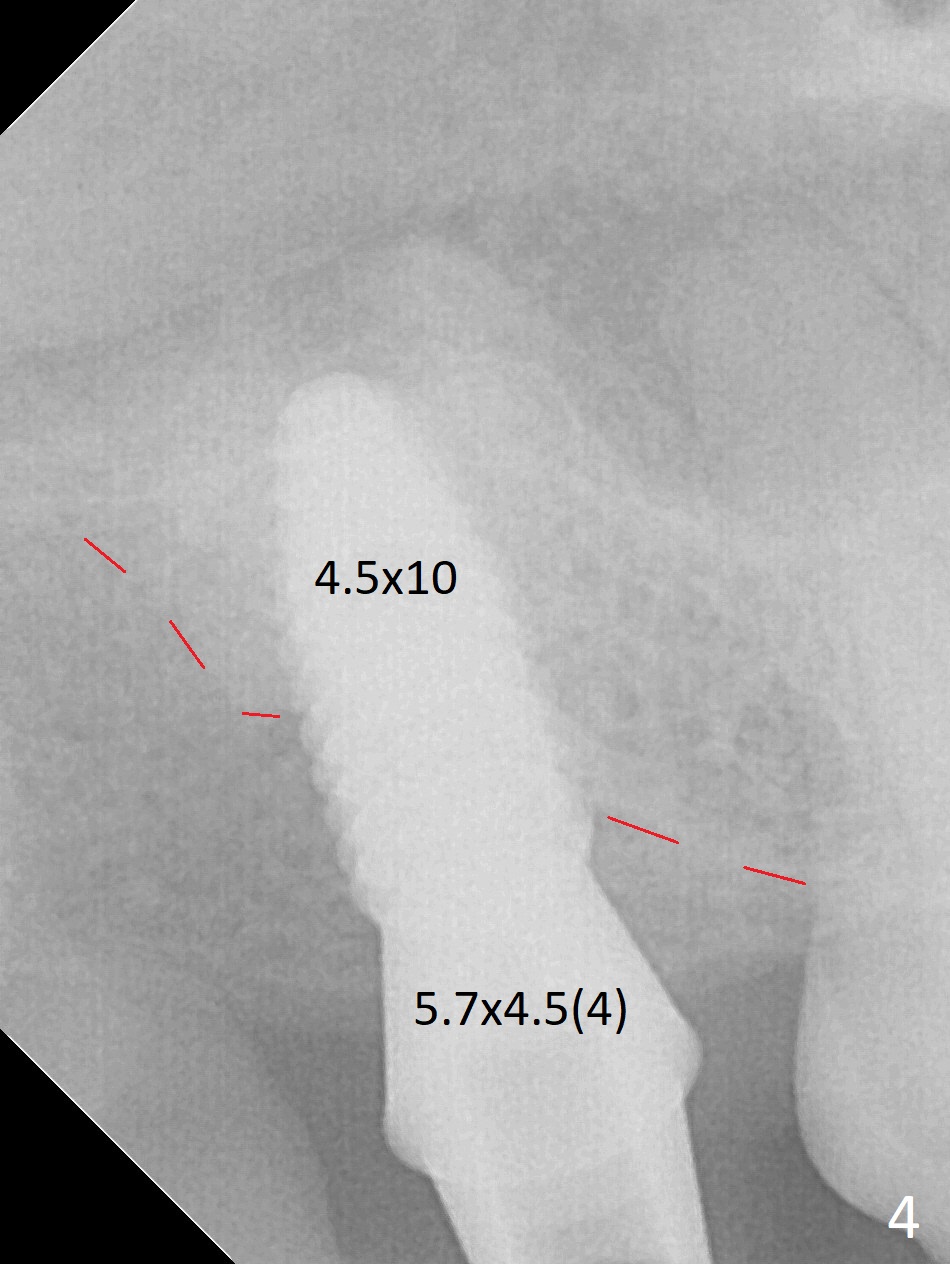

After extraction of the 3rd molar with mesial periodontal defect, osteotomy for 2nd molar implant is initiated in the mesial slope of the 3rd molar socket (Fig.1 red dashed line). When osteotomy is finished with IS drills and sinus lift with Magic Sinus Lifter (S-reamer with 11 mm stopper being short), a 4x10 mm dummy implant is placed with ~ 4 implant thread exposure (Fig.3). Following use of Lindamann bur to move osteotomy mesial and larger drill, a 4.5x10 mm implant is placed with 5-7 implant threads exposed distally (Fig.4,7 (~ 50 Ncm)). The bucco(B)-palatal(P) extent of the implant thread exposure is larger (Fig.5) than that associated with the 4 mm dummy implant (data not shown). The exposed implant surface is covered with Vera Graft (Fig.7*), Collagen plug and an immediate provisional after adjustment of abutment height (Fig.6,7). The bone density distal to the implant is low 3 months postop (Fig.8,9 CBCT) and 3.5 months postop (Fig.10,11). The permanent crown is cemented nearly 4 months postop. The distal cortical bone contacts the implant (Fig.12 ^), while the mesial bone increases in density (*) 2 years postop.